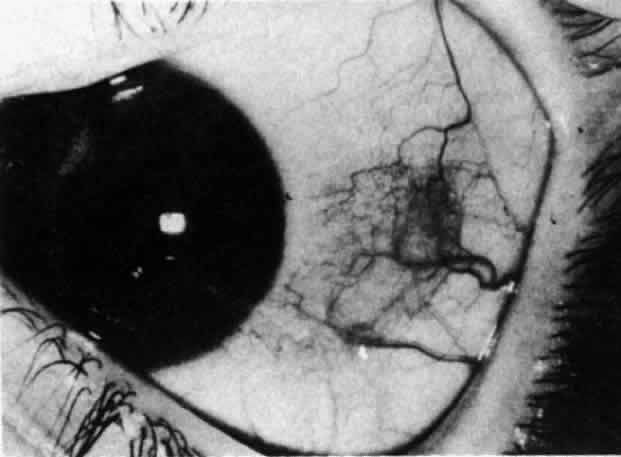

Pigmentation of the sclera may be either diffuse or localized to a single

discrete patch, and although it is more common in blacks or Asians, it

is still seen in whites. Strictly, the pigmentation is not congenital

because it appears shortly after birth from migration of chromatophores

through the sclera or via the perivascular channels in the anterior

sclera. It is not unusual to note a cuff of pigment around the exit

of the vessels from the sclera in blacks as a normal phenomenon, and

this is particularly noticeable near the limbus. The episclera can also

be diffusely pigmented, probably from the downward extension of the

pigment cells of the basal epithelium of the conjunctiva (Fig. 76). Very rarely, pigmentation of sclera in white races may indicate an intraocular